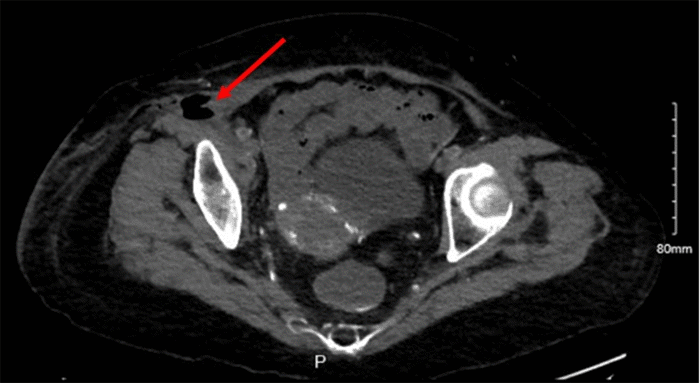

Computed tomography (CT) of the abdomen and pelvis demonstrated inflammation and gas within the right pelvic wall with 5 cm of complex fluid collection (Figure 2), and gas tracking along the psoas and iliacus muscles (Figures 3 and 4), suggestive of septic shock secondary to NSTI. Given the patient’s clinical presentation of septic shock, aggressive management was initiated with intravenous fluid resuscitation, broad-spectrum antibiotics, and reversal of coagulopathy using prothrombin complex concentrate and vitamin K. Subsequently, the patient underwent emergent surgical exploration and debridement of the infected right groin region.

Figure 3. Gas and Heterogeneity in Psoas Muscle. Published with Permission

CT Abdomen and Pelvis showing small bubbles of gas and heterogeneity of the psoas muscle